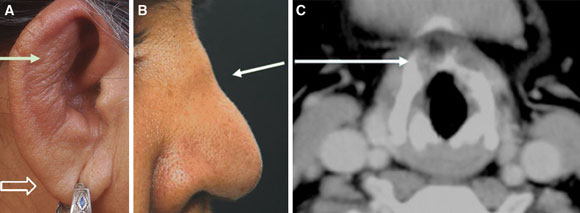

A 47-year-old woman presented with a 6-month history of fever, redness and pain in her ears and nose, and hoarseness of voice. She had redness and thickening of both ears (Figure A, solid arrow) with sparing of the lobule (hollow arrow), and a collapsed nasal bridge (Figure B). A computed tomography neck scan revealed destruction of the thyroid cartilage (Figure C). Antineutrophil cytoplasmic antibodies were negative, ruling out Wegener’s granulomatosis.